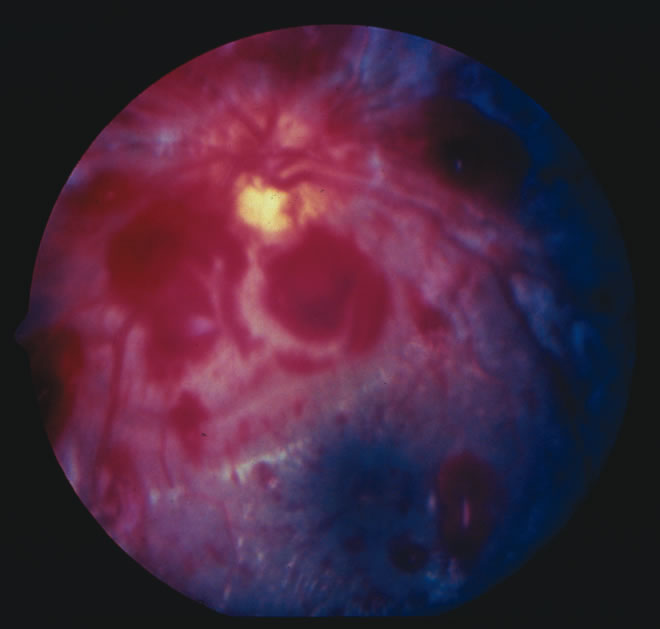

Findings range from a normal fundus to a small number of scattered intraretinal hemorrhages in the posterior pole to massive, confluent hemorrhages from the posterior pole to the ora serrata.(Fig. 10) The hemorrhages may be subretinal, deep intraretinal (dot/blot), nerve fiber layer (flame shaped) or preretinal.19,45 Intraretinal hemorrhages are more common than preretinal or subretinal hemorrhages.32,46 Preretinal hemorrhages must be distinguished from traumatic retinoschisis (see later), which has particular diagnostic significance. White-centered retinal hemorrhages, although classically associated with endocarditis, can occur in any condition that causes retinal hemorrhages, including SBS. Vitreous hemorrhage may be small to massive, and may occur secondary to escape of blood from intraretinal collections or from torn vessels.19 Although vitreous hemorrhage may occur at the time of injury, it may also be a delayed finding occurring 1 to 3 days or more after the initial trauma.47,48

The pathophysiologic mechanisms of retinal hemorrhage in SBS are varied. Vitreous and perhaps orbital shaking is likely to be involved in most of the vitreoretinal injuries. In children, the vitreous is well attached to the retina at the macula, blood vessels, and the periphery. Shaking of an infant causes the vitreous to shake, which, in turn, applies shearing forces to the retina at points of firm attachment. These shearing forces at the macula may split the retina at any layer, causing the formation of a cystic cavity, which may be filled partially or completely with blood (Fig. 11). This traumatic retinoschisis has been well documented in abuse cases by ultrasound, electroretinogram, and pathology.34,58,60,61,62,63,64 Histopathology reveals a widening of the retinal layers or a stripping of the internal limiting membrane. The vitreous may stay adherent or detach. Clinically, to recognize this important finding in SBS, the examiner may observe a hemorrhagic or hypopigmented curvilinear edge to the schisis cavity, with or without a fold in the retina (Figure 11).50,65,66 Recognition of this edge helps distinguish retinoschisis from subhyaloid hemorrhage. However, subhyaloid hemorrhage, which may have originated from blood breaking out of a schisis cavity, may obscure the underlying schisis. It is important to follow any potentially shaken child with preretinal blood in the macula until that blood has cleared as the signs of schisis may be unmasked as the blood resorbs thus confirming the diagnosis of SBS. The retinal fold or hypopigmented line may be a complete circle or just an arc. In the long term, these patients may have surprisingly few sequelae and good vision as the cavity flattens spontaneously. There may also be findings of permanent curvilinear, hypopigmented scars or retinal folds. These provide clues to prior abuse.67

There remain still other theories for retinal hemorrhage in SBS that also seem to play a minor role. Some have suggested a Purtscher-like mechanism due to an increase in intrathoracic pressure when the perpetrator squeezes the child's chest. Although the characteristic white retinal patches of Purtscher retinopathy may be seen in SBS (Fig. 11), there appears to be no correlation with rib fractures,35 and the finding is very uncommon. The failure to see significant retinal hemorrhaging after the chest compressions of cardiopulmonary resuscitation in both animal models and humans also argues against a Purtscher-like mechanism.

The differential diagnosis of retinal hemorrhages in a child is vast. However, if one considers a child with the full spectrum of injuries seen in SBS, including brain, skeletal, and eye findings, most would not dispute that the retinal findings are due to nonaccidental injury. However, in a child with a small number of retinal hemorrhages and without retinoschisis, (Fig. 10A) the diagnosis of SBS may be less clear.